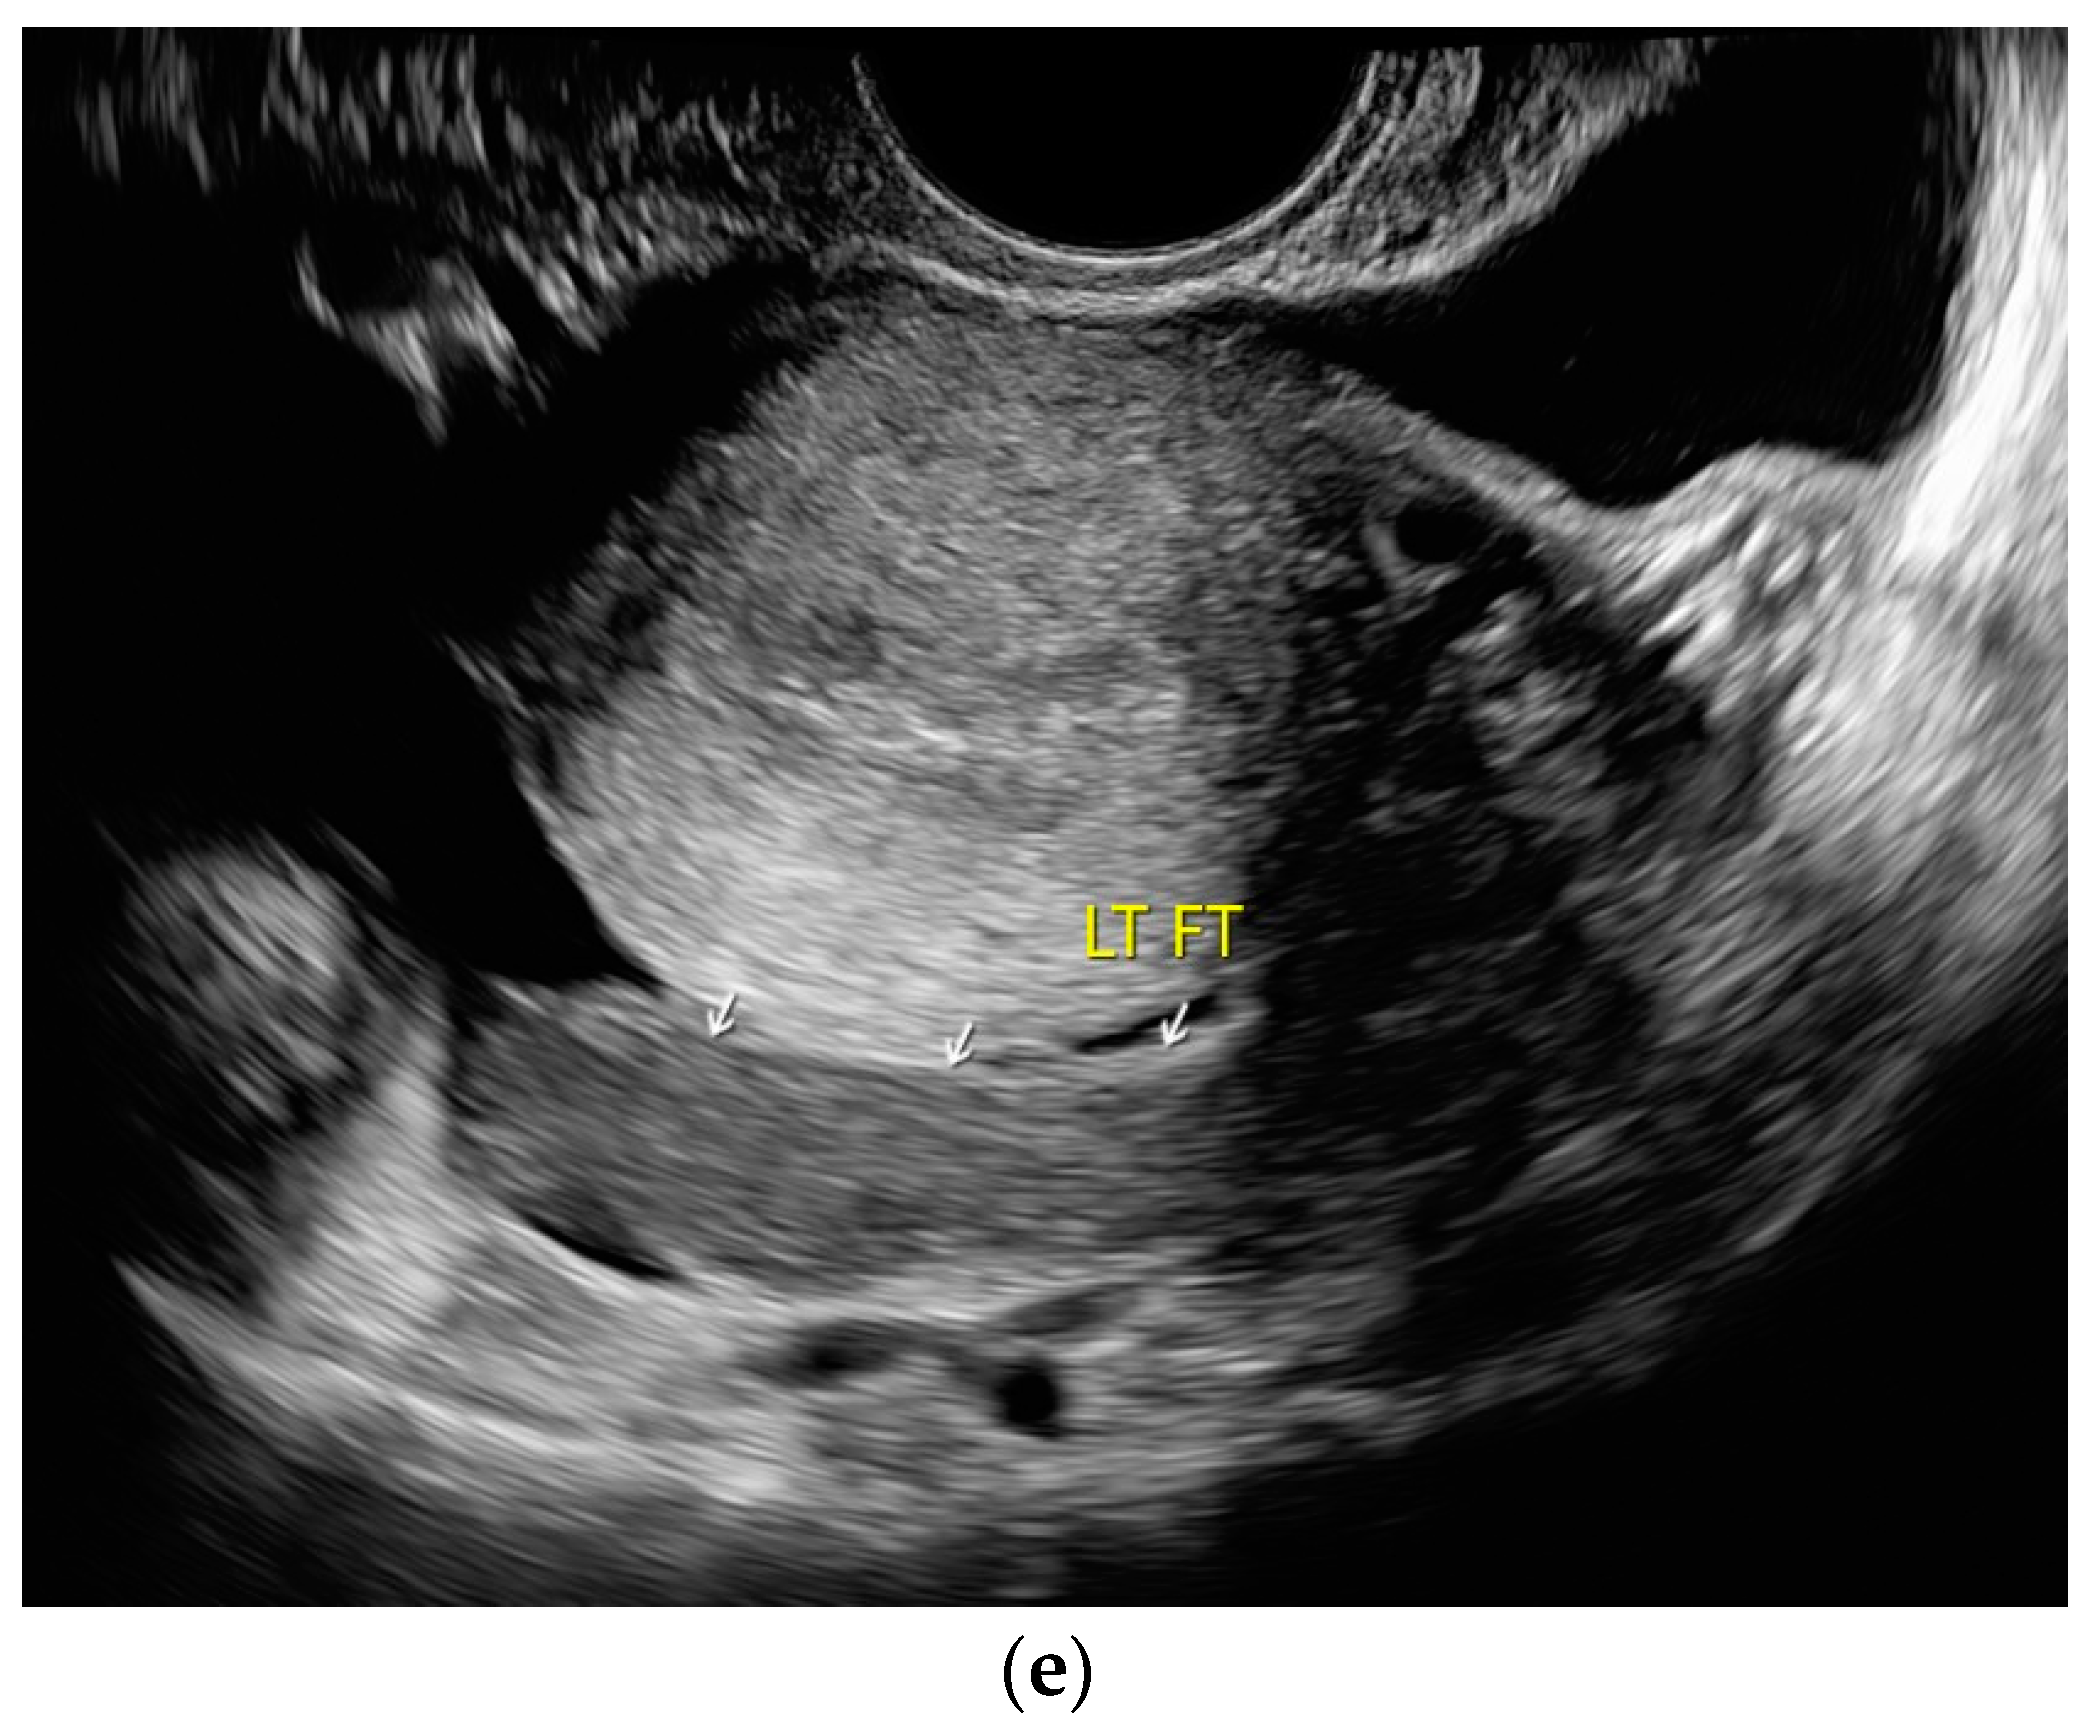

Figure 8.

Tuberculosis of the uterus and adnexae. Female patients with tuberculosis in India. Pelvis with tubo-ovarian masses: Hypoechoic lesion in right adnexa (arrows) (a) and hypoechoic lesion in left adnexa and a small amount of free fluid (arrows) (b). Free fluid in the Douglas space (arrows) (c). Thickened right fallopian tube (RT FT) (arrows) (d); thickened left fallopian tube (LT FT) (arrows) (e).